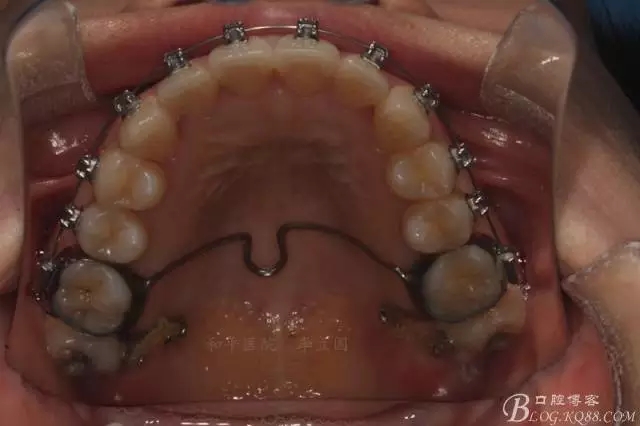

該病例主要為17、27頰側(cè)位同時(shí)伴有伸長,當(dāng)然種植支抗可以解決,但還有簡單實(shí)用的辦法嗎?如圖,在橫腭桿遠(yuǎn)中延伸出牽引鉤,位置盡量遠(yuǎn)離合平面,7粘舌側(cè)扣,牽引力的方向?yàn)閴旱图吧嘞?,下圖為兩個(gè)月的效果,17已到位,27還未到位。